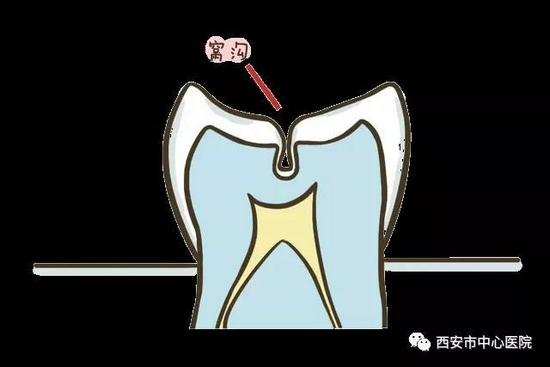

很多人都从这样或那样的渠道听说过窝沟封闭。那么,什么是窝沟封闭?它到底封闭了个啥?

所谓窝沟封闭是指不损伤牙体组织,将窝沟封闭材料涂布于牙冠咬合面、颊舌面的窝沟点隙,当它流入并渗透窝沟后固化变硬,形成一层保护性的屏障,覆盖在窝沟上,能够阻止致龋菌及酸性代谢产物对牙体的侵蚀,以达到预防窝沟龋的方法。

它封闭了较深的窝沟,使咬合面变得光滑,避免了食物残渣在此存留,并使原本不易清洁的牙面变得利于清洁与自洁。

它封闭了致龋菌进入窝沟深处的通道,使窝沟深处釉质较薄,抗龋能力差的缺点得以规避,断绝了窝沟龋发生的途径。